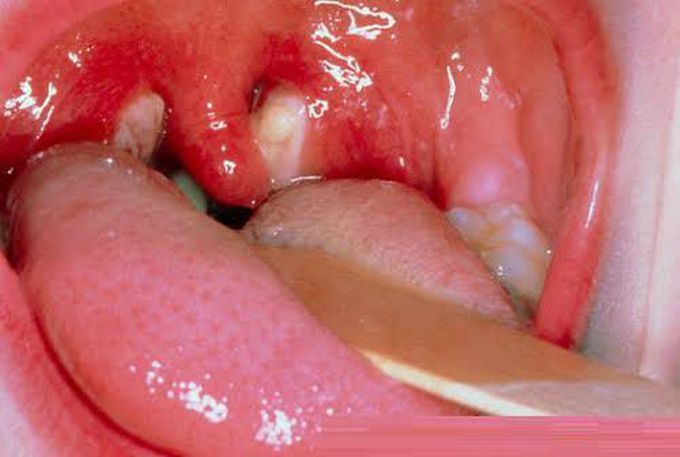

Glandular fever is caused by the Epstein-Barr virus (EBV). This virus is found in the saliva of infected people and can be spread through: kissing – glandular fever is often referred to as the "kissing disease" exposure to coughs and sneezes sharing eating and drinking utensils, such as cups, glasses and unwashed cutlery EBV may be found in the saliva of someone who has had glandular fever for several months after their symptoms pass, and some people may continue to have the virus in their saliva on and off for years. If you have EBV, it's a good idea to take steps to avoid infecting others while you are ill, such as not kissing other people, but there's no need no need to avoid all contact with others as the chances of passing on the infection are generally low.